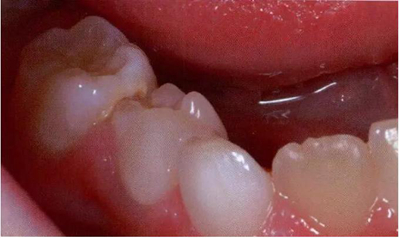

圖8展示了一張5歲孩子右下第二乳磨牙嚴重下沉的口內(nèi)像。臨床檢查可見右下第一乳磨牙遠中傾斜,朝向下沉乳牙。X線片檢查顯示所有恒牙胚都存在(圖9)。無論是臨床還是影像學,都可檢查到有齲齒的存在。鑒于這顆下沉乳牙在年齡較小時就已經(jīng)非常嚴重,同時還患有齲病,因此決定予以拔除。后期在放置間隙保持器的同時還應持續(xù)觀察監(jiān)測右下第一恒磨牙和第二前磨牙的萌出情況。

文獻直達|乳磨牙下沉的臨床管理

圖8:一名五歲患兒右側(cè)下頜第二乳磨牙嚴重下沉臨床像